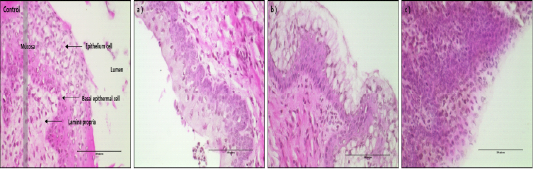

H&E-stained vaginal tissues after 24hr of treatment with D1, D2 and D3 (magnification, X400). Black bar=100 um. Control group: Normal vaginal epithelium cell of mice, a) D1 treatment group, b) D2 treatment group, c) D3 treatment group.

A: H&E staining of mouse vagina epithelial cells treated with D1, D2 and D3. B: Microscopic image analysis of mouse vagina epithelial cells for different treatment groups.